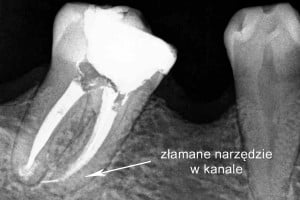

– perforacja kanału lub złamane narzędzie w kanale